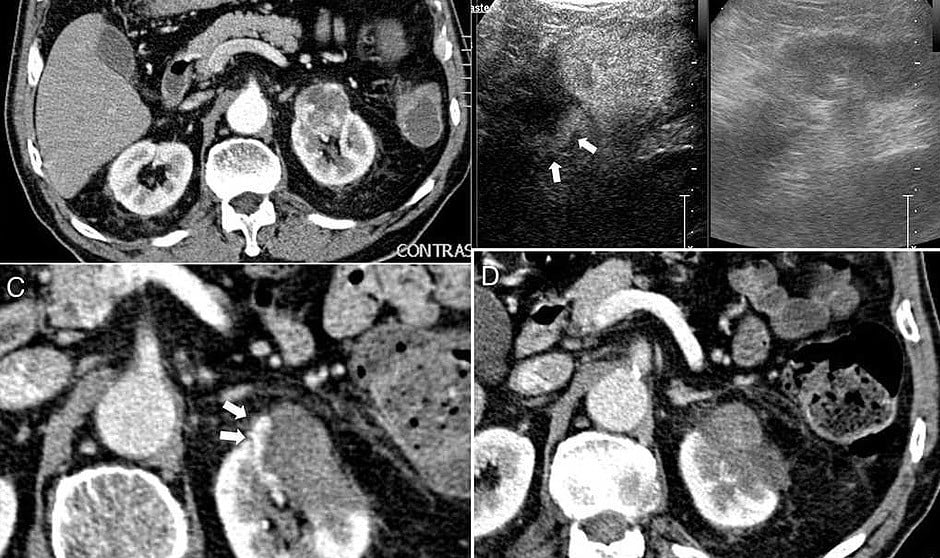

La ablación percutánea es una técnica de aplicación de energía generadora de calor (radioablación) o de frío (crioablación) que se da en el interior de la lesión. Según un último estudio, publicado por la editorial Elsevier, esta técnica aplicada en tumores renales tiene una "altísima eficacia", tal y como declaran los investigadores en el trabajo.

Aspectos prácticos de la ablación por radiofrecuencia en tumor renal

Además de esta investigación, un grupo de investigadores españoles llevaron a cabo otra sobre los aspectos prácticos que puede tener la ablación por radiofrecuencia en tumores renales. Los resultados de esta fueron que "la ablación por radiofrecuencia en este tipo de tumores en manos experimentadas y con una selección apropiada de los tumores (tumores r3,5 cm y de localización exofítica) puede conseguir excelentes resultados oncológicos con una mínima morbimortalidad", señalan los principales investigadores de este trabajo.

Los resultados de este último estudio, llevado a cabo por el Hospital Universitario de Córdoba y publicado en la revista de la Sociedad Española de Radiología Médica (SERAM), demostraron que "el tamaño medio de los tumores fue de 2,8 centímetros y se consiguió necrosis completa en 17 tumores, un 85 por ciento". Además, el estudio subraya que "en 15 de 16 tumores de 3,5 centímetros o menos se logró realizar la ablación completa".